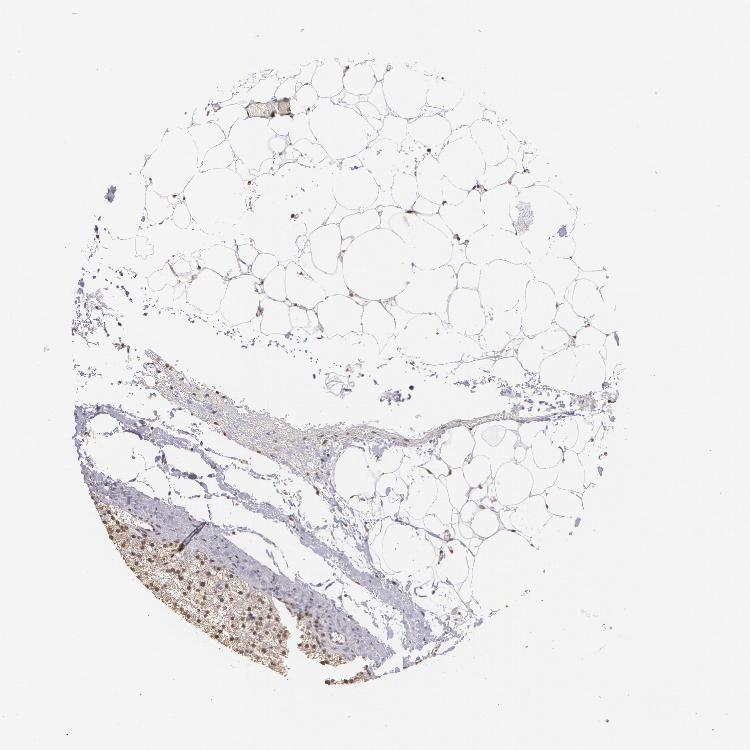

ADRENAL GLAND - Antibody stainingi

Antibody staining in the annotated cell types in the current human tissue is reported as not detected, low, medium, or high, based on conventional immunohistochemistry profiling in selected tissues. This score is based on the combination of the staining intensity and fraction of stained cells.

Each image is clickable and will lead to virtual microscopy that enables deeper exploration of all samples and also displays staining intensity scores, fraction scores and subcellular localization as well as patient and tissue information for each sample.

Antibody CAB002008Antibody CAB002009

Glandular cells MediumMedium